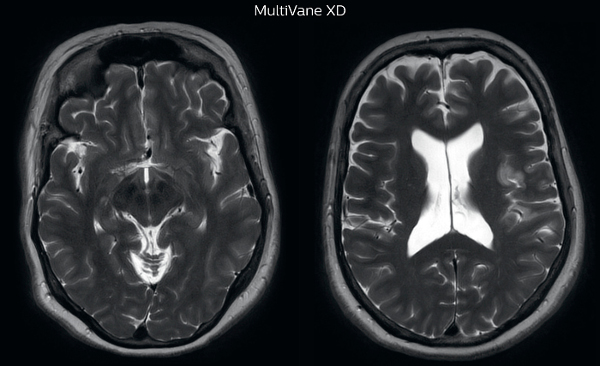

The images made with MultiVane XD show significant reduction in motion artifact compared to the T2-weighted images without MultiVane below them. Scanned on Ingenia 3.0T

“Motion artifacts can obscure subtle findings, make image interpretation more difficult and decrease diagnosis confidence. For example, when imaging the cerebellum or brain stem, or when looking for subtle multiple sclerosis (MS) lesions, motion can be problematic,” says Dr Nickerson. MultiVane XD motion-free imaging delivers diagnostic images even in the case of severe patient motion. A more relevant patient group is one with typical small artifacts related to moderate motion like an occasional cough. The absence of those artefacts brings forth better day-to-day diagnostic confidence. MultiVane XD works in multiple orientations and for various contrasts, such as T1-weighted, T2 weighted and FLAIR. Trevor Andrews, PhD, explains that the team compared motion artifacts seen in the brain with MultiVane XD and with T2-weighted TSE. “In nine out of the ten datasets in our studywe saw clear improvementswith MultiVane XD, while in the tenth dataset image qualitywas comparable. The MultiVane XD sequence is now used in the majority of patients that present at UVM for brain MRI.”

“We saw MultiVane XD provide remarkable improvement, not only for artifacts caused by patient motion, but also for the extent of pulsation artifacts in the basal cisterns. Based on these results, we have added the MultiVane XD sequence to our brain studies,” says Dr. Nickerson. “MultiVane XD is especially useful when imaging patients with diseases that cause white matter changes on T2-weighted images, such as MS, small vessel disease, vasculitis and sarcoidosis,” says Dr. Nickerson. “Many of these are only visible on T2-weighted or FLAIR images, and sometimes aren’t even seen with FLAIR images. However, when using MultiVane XD and we don’t see any motion on the rest of the scan, but still do see a signal abnormality, we can probably attribute that to a real disease process, rather than an artifact.”